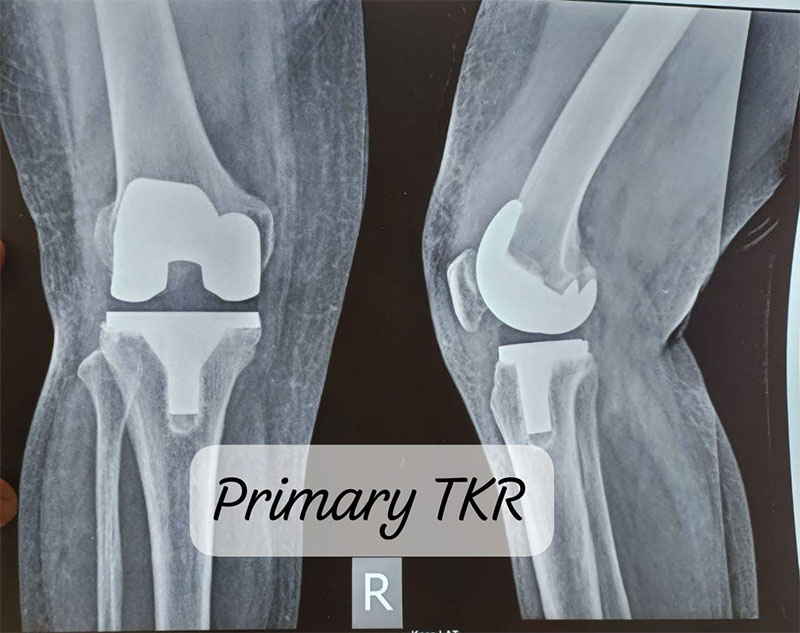

Primary Knee Replacement and Revision Knee Replacement are surgical procedures related to the knee joint, commonly performed to relieve pain and restore function in patients with severe arthritis or knee damage.

Primary knee replacement is the first surgery a patient undergoes to replace a damaged or worn-out knee joint. It is typically performed for conditions like osteoarthritis, rheumatoid arthritis, or traumatic injury to the knee joint.